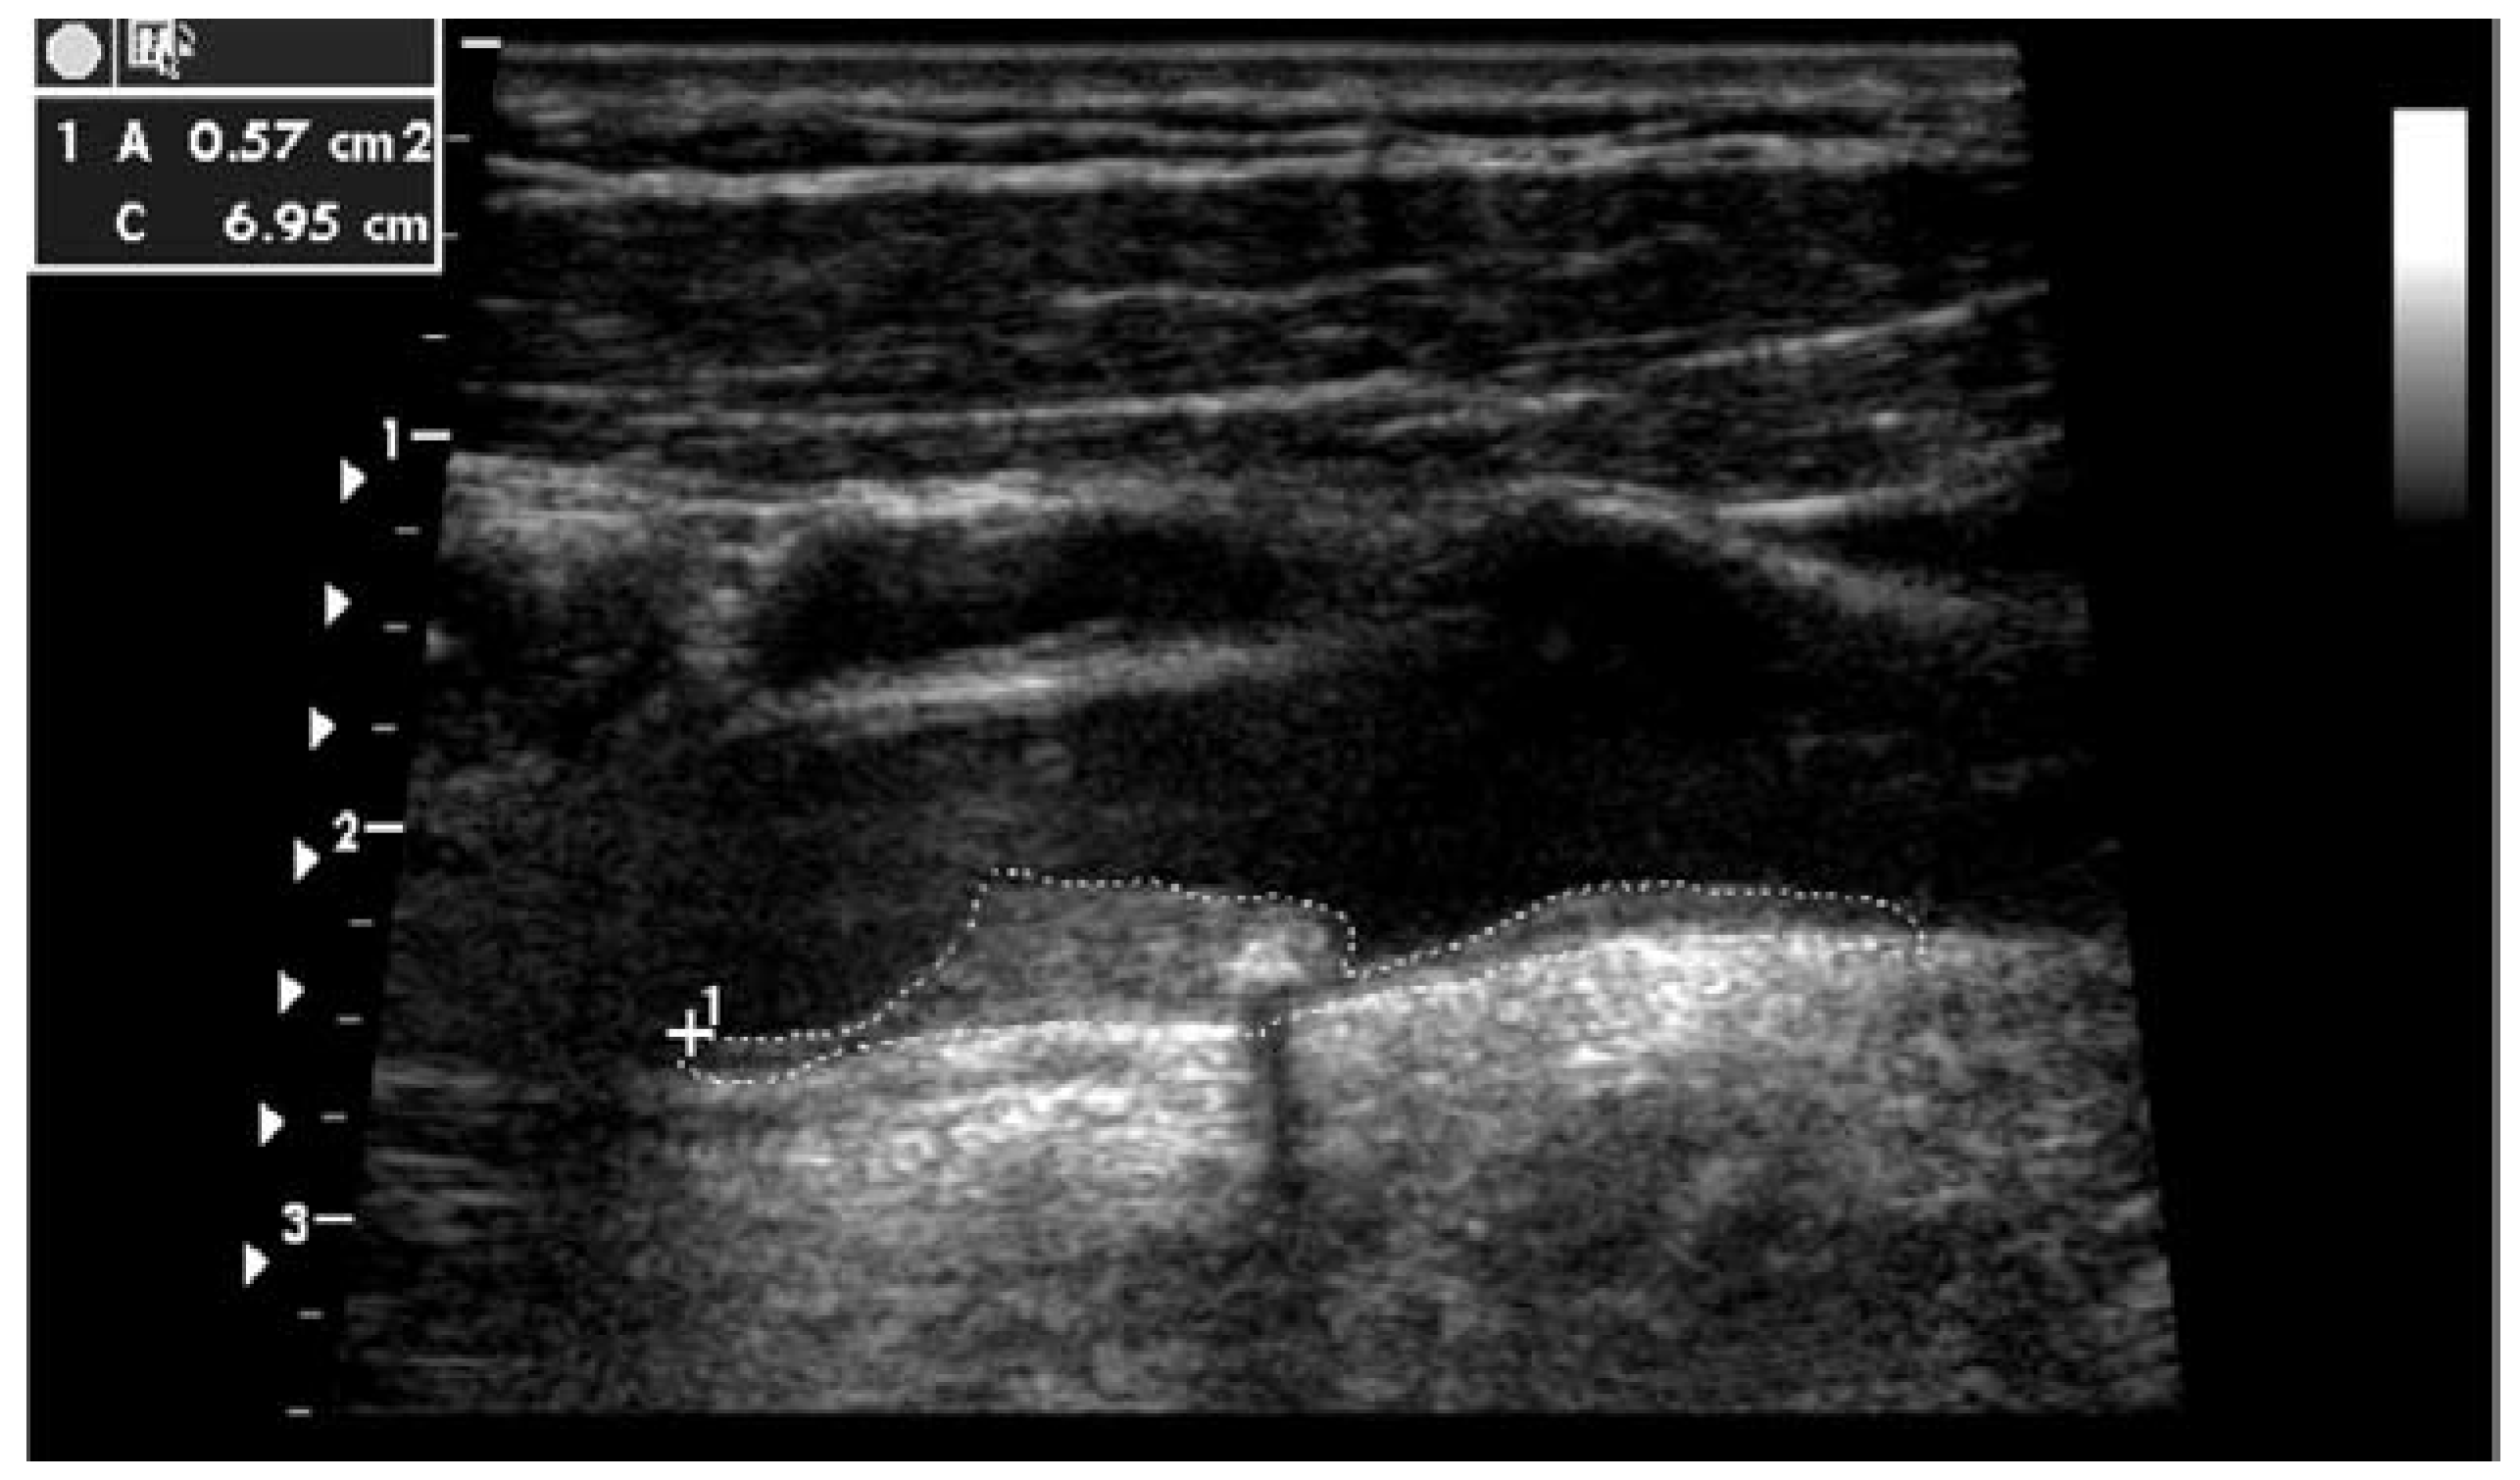

Imaging method and risk assessment using total plaque area of carotid arteries (TPA)

Total plaque area (TPA) is a measure of the total plaque burden of the carotid arteries. Plaques are traced longitudinally, and the TPA is derived from the sum of all plaque areas detected during the imaging of both carotid arteries. Imaging was done with the patients in the supine position as described in the original London cohort [7]. During examination of the carotid artery, the patient was brought into a position that allowed head rotation to both sides. The sonographer stood to the right of the patient’s chest. The head was rotated 35–45° away from the side being examined and retroflexed by approximately 10–20°. Imaging was started with a transverse (short-axis) sweep to check for the presence of plaque (defined by a thickening >1 mm) and included the total length of the common carotid artery, the bulb, and all visible parts of the internal and external carotid arteries. Plaque quantification was made from a longitudinal image. Online tracing of the plaque surface area was performed by using calipers. The sum of all plaque surface areas was defined as the TPA (Figure 2).

Figure 2. Qualitative and quantitative display of a common carotid artery plaque traced longitudinally.